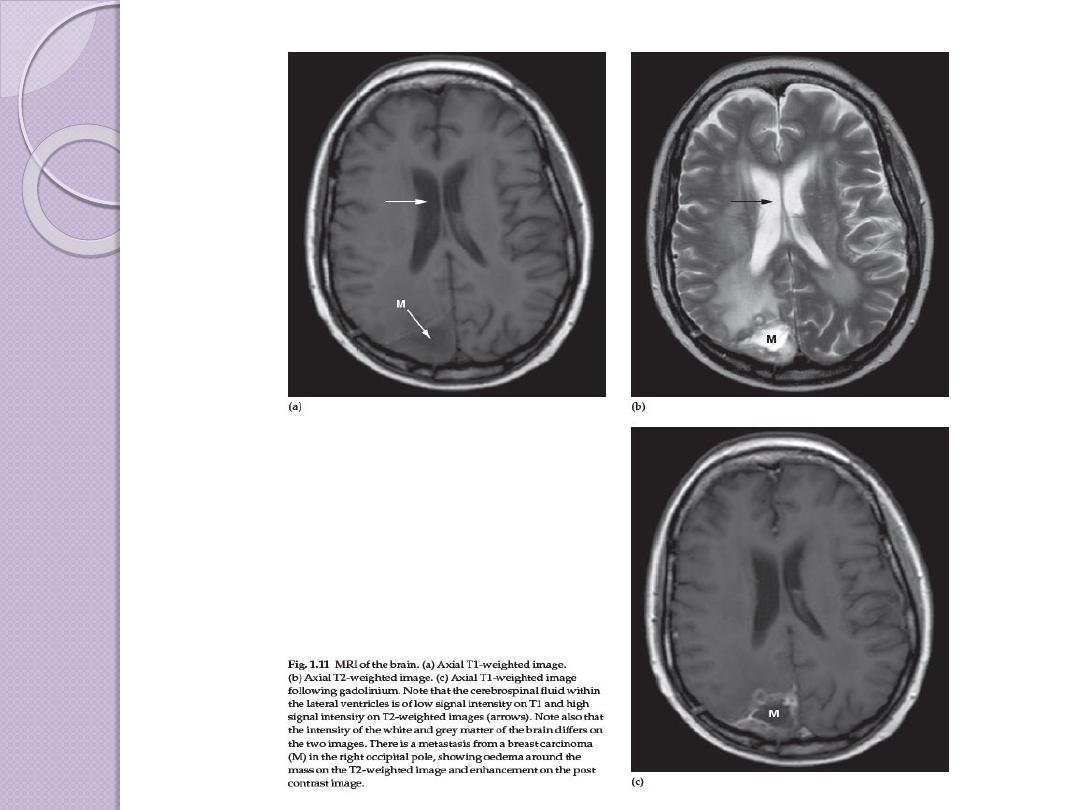

Brain Tumor Imaging

What’s changed between these images?

T

1

-weighted Sagittal

T

1

-weighted Axial

T

2

-weighted Axial